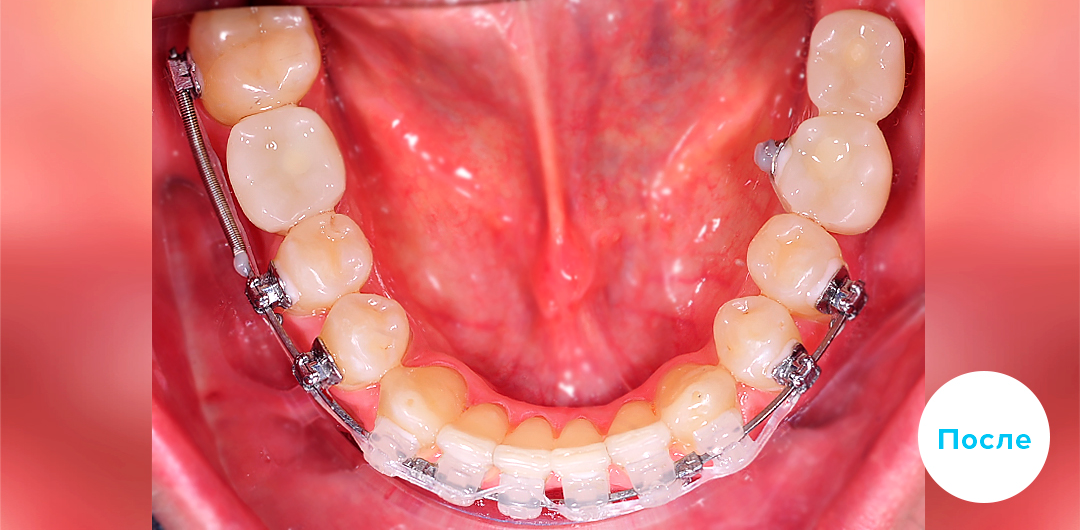

Результаты лечения